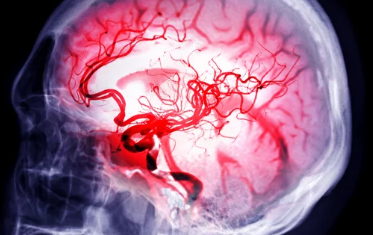

뇌졸중, '골든타임'을 놓치지 마세요! ⏰ 전조 증상 6가지, 꼼꼼하게 체크하고 빠르게 대처하자!

갑작스러운 두통, 어지럼증, 한쪽 팔다리 마비... 이러한 증상들은 뇌졸중의 전조 증상일 수 있습니다. 뇌졸중은 뇌혈관이 막히거나 터져서 발생하는 질환으로, 빠른 진단과 치료가 매우 중요합니다. 하지만 많은 사람들이 뇌졸중 전조 증상을 가볍게 여기거나 다른 질환과 혼동하여 치료 시기를 놓치는 경우가 많습니다. 오늘은 뇌졸중 전조 증상을 자세히 알아보고, 응급 상황 발생 시 대처 방법과 예방법까지 꼼꼼하게 살펴보겠습니다.